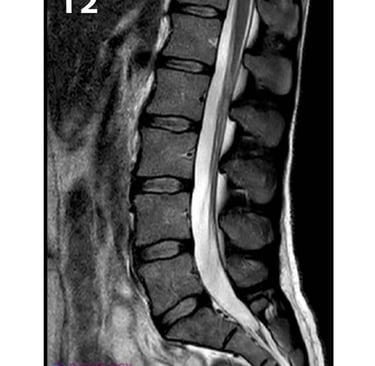

Moments capturing expert trauma and orthopedic care in action